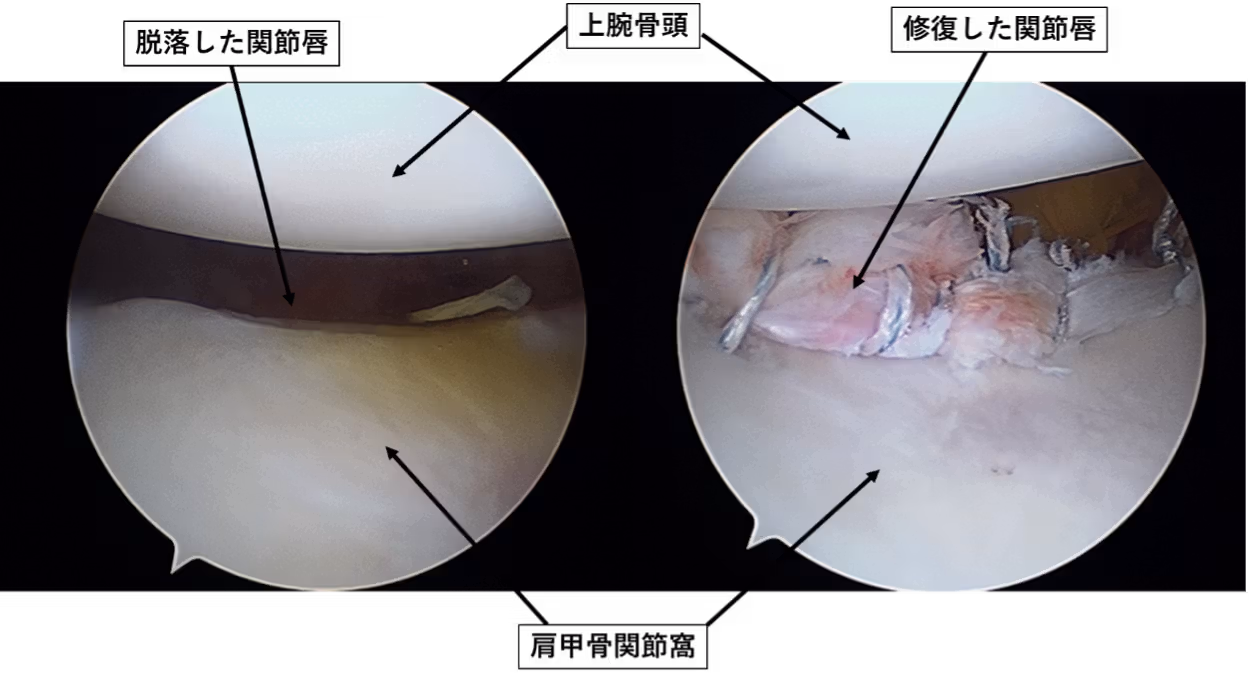

肩関節は非常に不安定な関節で人間の関節の中で最も脱臼しやすい関節です。若年(10代、20代)で初回脱臼をおこすと高率で反復性に移行します。反復性になると、日常生活に支障をきたしたり、将来的に変形性関節症を引き起こす危険性が高くなります。脱臼を制動している関節包と関節上腕靱帯が脱臼の際に靱帯の根元である関節唇ごと肩甲骨関節窩(受け皿)から剥がれています。関節窩にアンカーという糸付きのネジを挿入して、関節唇・関節上腕靱帯に糸をかけて関節窩に縫縮します。術後は三角巾固定を3週間程度おこない、6週間程度外旋動作は禁止します。日常生活は2~3ヶ月で復帰、スポーツ復帰は種目によりますが術後6ヶ月程度で復帰となります。